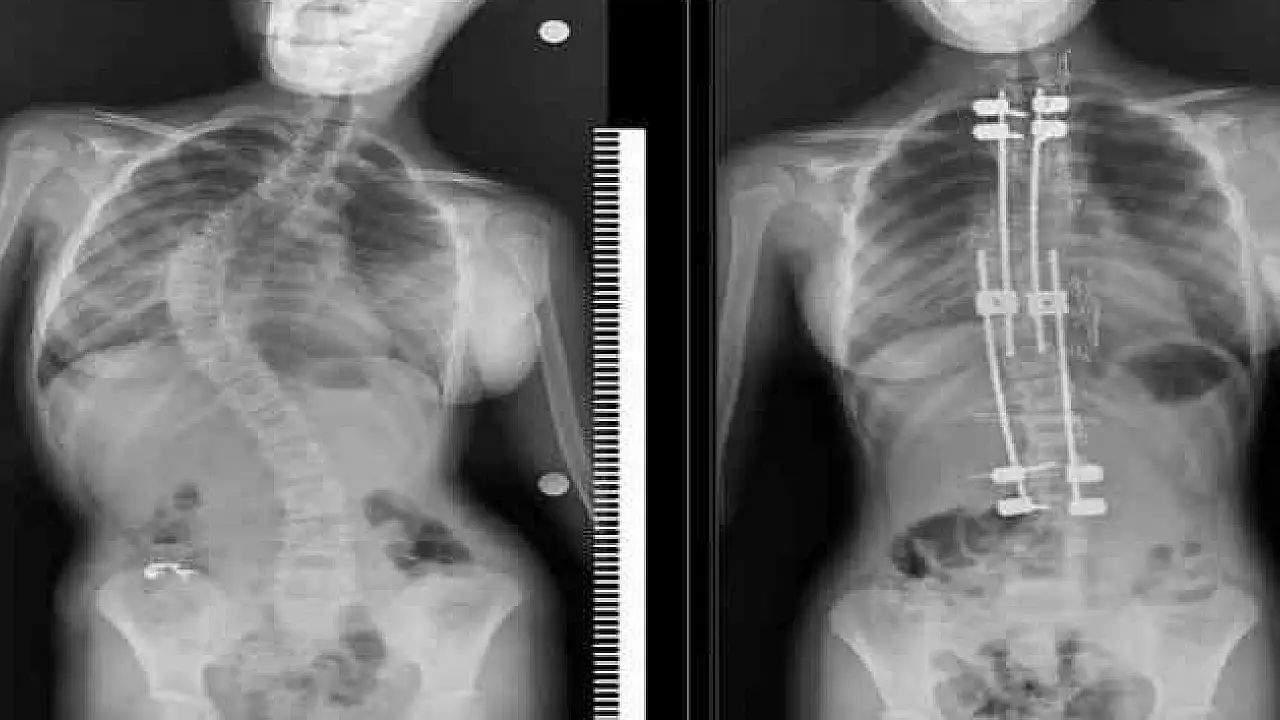

İleri derecede eğriliklerde cerrahinin bir seçenek olarak gündeme gelebileceğini söyleyen Üçpunar, ameliyat sonrası yaşamla ilgili endişelerin abartıldığını belirterek şunları kaydetti:

“Güncel bilimsel veriler, skolyoz cerrahisi geçiren çocukların yaşam kalitesinin sağlıklı yaşıtlarıyla neredeyse aynı olduğunu gösteriyor. Modern teknikler sayesinde bu hastalar eğitimlerine dönebiliyor, meslek sahibi olabiliyor ve sosyal yaşamda aktif yer alabiliyor. Cerrahi, bu sürecin sonu değil; pek çok çocuk için yeni bir başlangıçtır.”